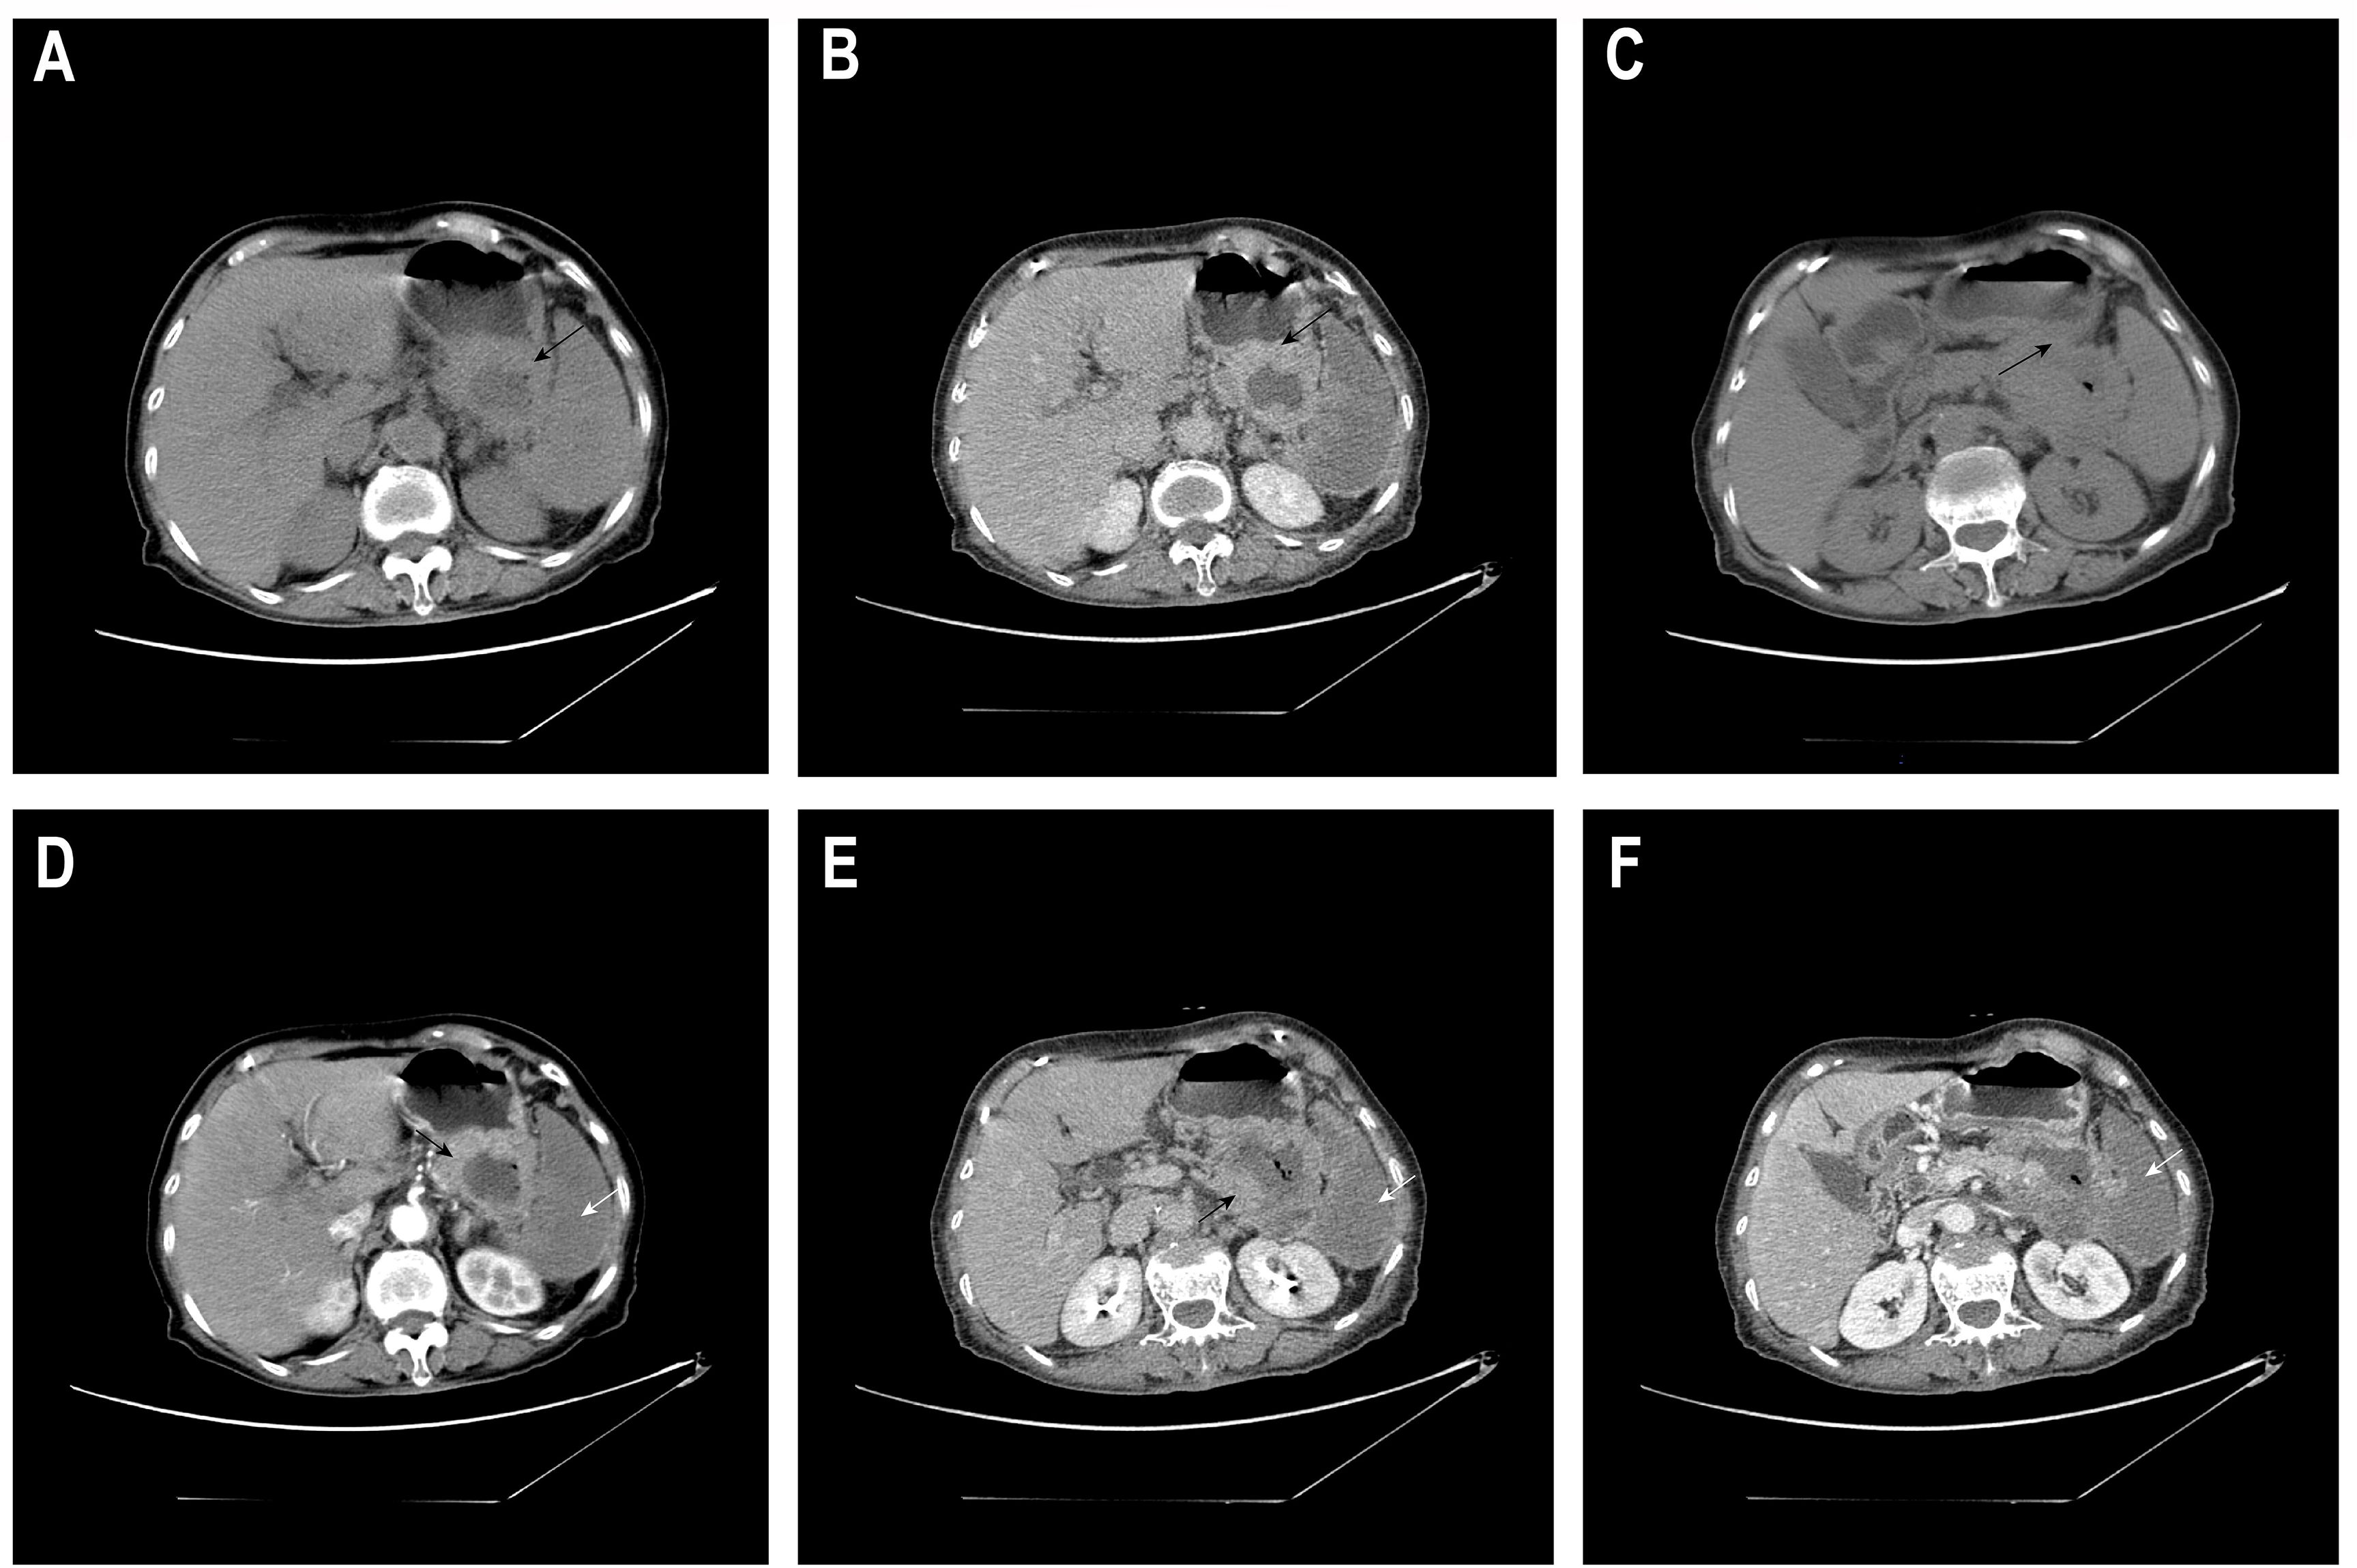

Objective: To report the diagnosis and treatment of a rare case of primary gastric squamous cell carcinoma (PGSCC) in an elderly female, and to explore the diagnostic pitfalls and individualized treatment strategies. Methods: We conducted a retrospective analysis of the clinical, imaging, endoscopic, and pathological data of a 77-year-old female patient. The evolution of the diagnosis from the initial "possible adenocarcinoma" to the final diagnosis of " squamous cell carcinoma" was emphasized. Results: The patient presented with abdominal pain. The first endoscopic biopsy, due to the limited tissue sample, showed immunohistochemistry results of CKpan (+), CK7(+), MUC5AC (focal+), and Ki-67(partly+), favoring a diagnosis of adenocarcinoma. A subsequent deep biopsy with complete immunohistochemistry (CK5/6+, P40+, P63+) confirmed the diagnosis of gastric squamous cell carcinoma. Given the patient's advanced age, poor physical condition, and refusal of surgery, a palliative treatment plan of "Raltitrexed + Sintilimab" was finally decided upon after a multidisciplinary consultation. Conclusion: This case highlights the importance of adequate sampling in the diagnosis of gastric squamous cell carcinoma to avoid misdiagnosis due to limited specimens. It also provides a potential treatment option of immune therapy combined with low-dose chemotherapy for elderly patients with gastric squamous cell carcinoma who are not suitable for surgery.